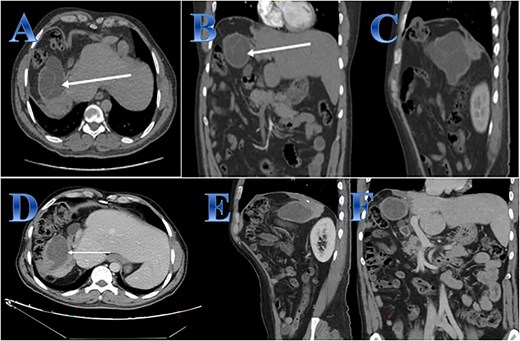

A 55-year-old male with a history of right hemi-hepatectomy secondary to a liver CE occupying the right hemi-liver; he presented with a 2-week history of epigastric and right upper quadrant pain radiating to the right shoulder pain with mild epigastric tenderness. An abdominal US revealed a cyst in the right lobe, no dilated IHBRs. The patient was started on albendazole and reevaluated again after 2 months with a CT scan. Abdominal CT showed a regressive course of the previously reported cystic lesion, seen as a well-defined cystic lesion at the right hepatic lobe measuring 6 × 4.4 × 5 cm while previously measuring 8.8 × 6.5 × 8.2 cm at AP, transverse, and vertical dimensions, respectively (Fig. 6).

Case 6. (A, B & C) Before treatment; residual small part of right hepatic lobe is seen with irregular borders and calcifications (post-operative changes) evidence of well-defined cystic lesion seen related to the anatomical site of the resected right hepatic lobe with internal septations that showed faint septal post contrast enhancement. (D, E, F) After treatment; regressive course of previously reported cystic lesion. Interval regressive course of the previously seen well defined cystic lesion seen at right hepatic lobe measuring 6 × 4.4 × 5 cm while previously measuring 88 × 65 × 82 mm at AP, transverse, and vertical dimensions respectively.